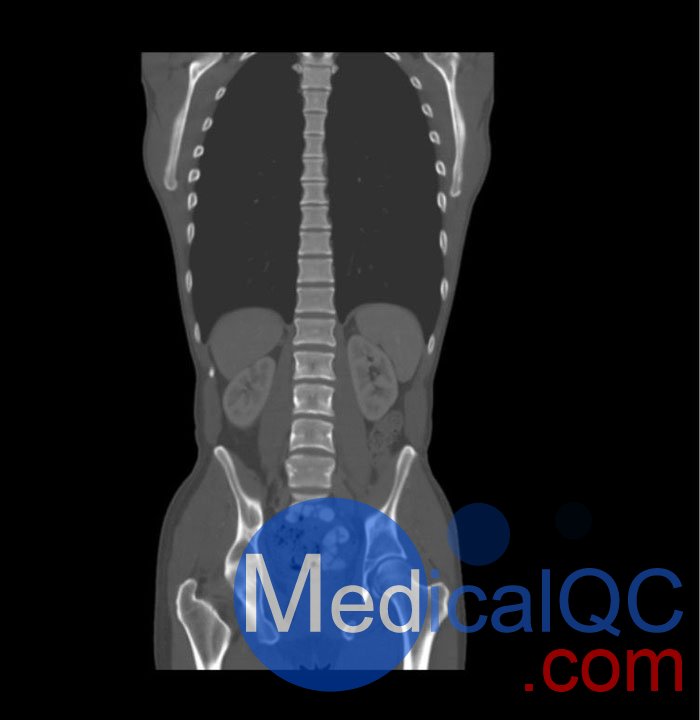

WEK57-01門靜脈期軀干模體,WEK57-01軀干模型模擬了門靜脈期的造影劑增強胸部、腹部和骨盆。它覆蓋了會陰的第二胸椎。

右側有髂淋巴結腫塊。

該模型可用于 CT(包括 CBCT)以評估和優化成像性能和后處理應用,包括支持 AI 的應用。它也適用于培訓目的。

該模型提供了對軟組織和骨組織的詳細而逼真的模擬。包括肺在內的空隙充滿了大約 -160HU的纖維素聚合物復合材料。

真實模擬脈管系統、骨骼和軟組織,包括肺、心臟、肝臟、膽囊、胰腺、脾臟、腎上腺、腎臟、胃、小腸、結腸、膀胱和前列腺。

右側髂外淋巴結腫塊。

大小: 約 267 x 185 x 466 mm

重量: 約 11040 g

基材: 纖維素-聚合物復合材料

最佳管電壓: 120 kVp – 可根據要求進行調整

WEK57-01門靜脈期軀干模體,WEK57-01軀干模型成像效果圖: